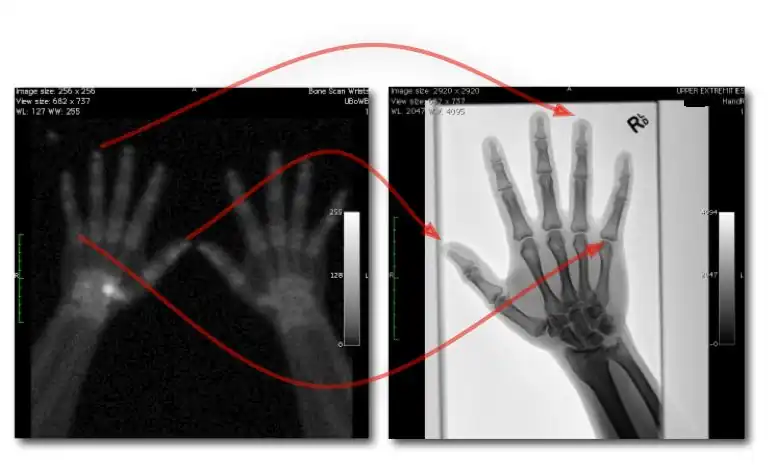

- Dual exposures: where two separate exposures are used in applications where patient movement isn't an issue; and